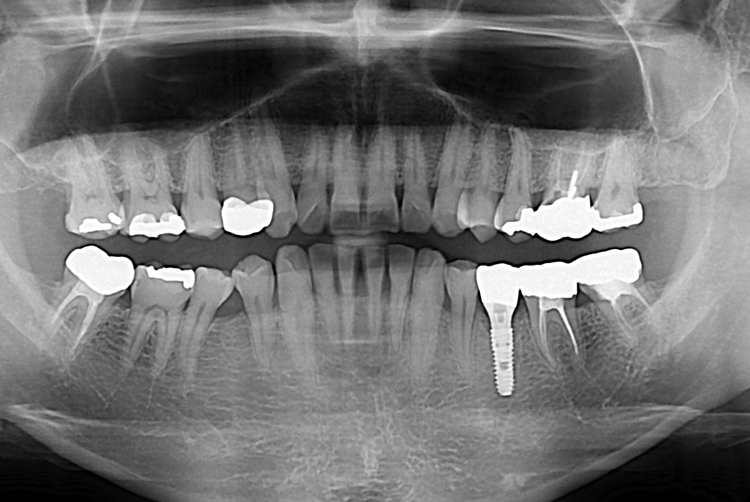

[임플란트] 어금니 임플란트

치료전 : 2019-06-19